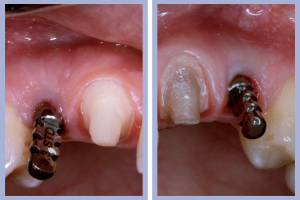

- Figg. 15a, b – Inserimento e preparazione del moncone temporaneo di destra

- Figg. 16a, b – Consegna della corona provvisoria in resina di destra

- Figg. 17a, b – Inserimento e preparazione del moncone temporaneo di sinistra

- Fig. 18 – Consegna della corona provvisoria in resina di sinistra

– Posizionamento e preparazione dei monconi temporanei (Figg. 15-20);

– Adattamento e consegna delle corone provvisorie (Figg. 15-20).

Il posizionamento implantare è stato seguito dal posizionamento e dalla preparazione intra-orale dei monconi temporanei e dalla successiva consegna, previa ribasatura, delle corone provvisorie. Durante la fase di attesa dell’osteointegrazione degli impianti si procedeva alla preparazione protesica dei canini (nella posizione dei laterali) per ottenere, tramite ricopertura protesica, la forma degli incisivi laterali.